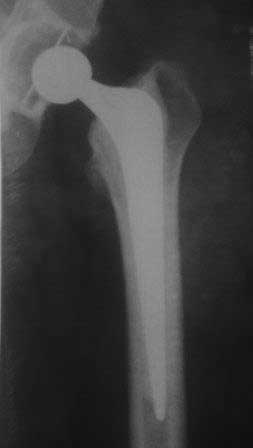

далее снимок у меня на приеме

С последним, третьим снимком он ко мне и обратился, после чего он был и прооперирован на правом тазобедренном суставе!

В дополнение к моему вышеуказанному пациенту. Досылаю послеоперационный снимок, который я не выслал сразу.

В конце 2008 года отметил боли в правой паховой области при опоре на правую ногу. На рентген снимках таза с тазобедренными суставами явных признаков нестабильности вертлужного компонента не обнаружено. В 2009 году нейрохирурги его "успешно" прооперировали на L\3-\4 связывая болевой синдром в правой паховой области с наличием грыжи указанного межпозвонкового диска. Состояние только ухудшилось, больной уже не мог долго сидеть, боль прогрессировала . Его в 2009 и 2010 годах смотрел ортопед, делались рентгенснимки, но почему то приходили к выводу что эндопротез справа стабилен. В марте 2011 года я впервые увидел его, через одну неделю после этого был прооперирован. На операции вертлужный компонент при упоре на него инструментом прокручивался во впадине и без труда был извлечен.

Расшорошили вертлужную впадину (дебридмент) Заменили чашку,учитывая невозможность полностью исключить инфекционный генез нестабильности, установили вертлужный компонент цементной фиксации (цемент с ванкомицином), поменяли головку из-за изменившихся взаимоотношении между бедренным компонентом и новой чашкой. Рану зашили наглухо. Провели антибактериальную терапию Кубицином. Выписали на 10 сутки после операции. Болевой синдром купирован, пациент радостный, уехал к себе в Калугу. Приедет на контрольный осмотр через месяц.